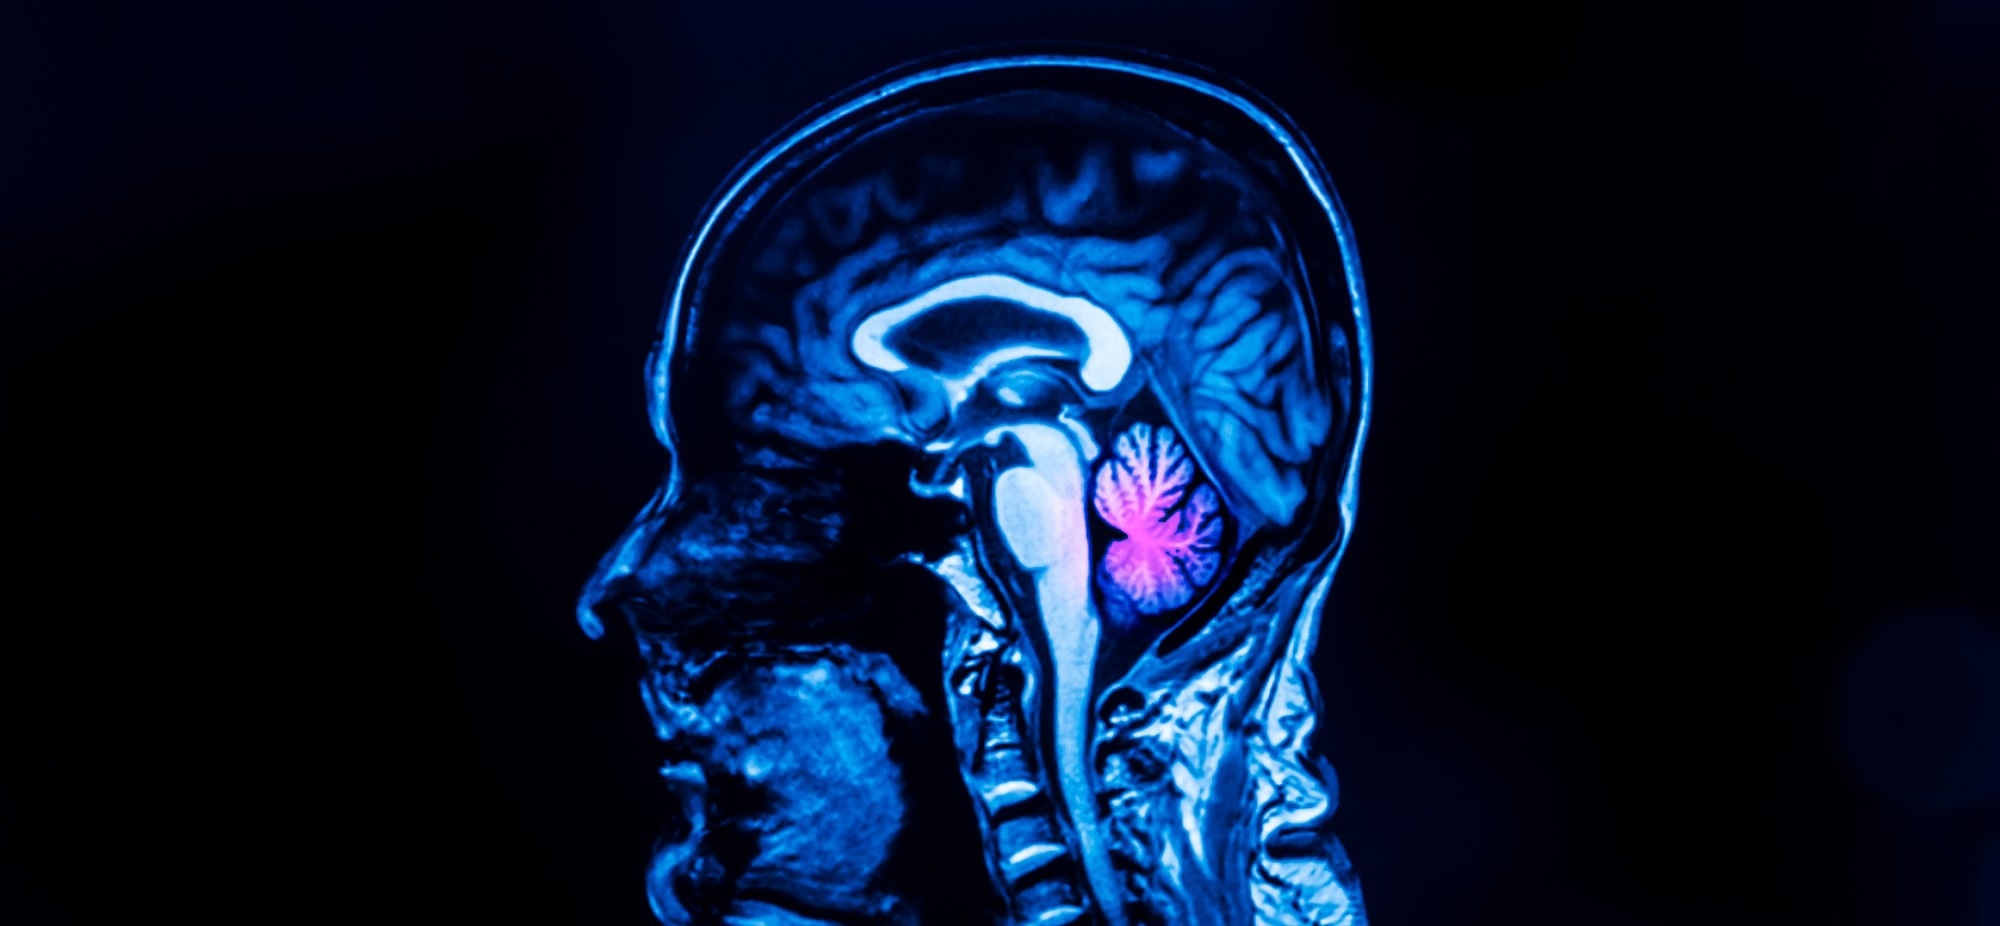

Cerebellar agenesis is a condition in which the normal formation of the hindbrain is disrupted. Patients with this disorder have very few pieces of cerebellar tissue - frequently the remains of lower cerebellar peduncles, anterior vermal lobules, and flocculi.

Cerebellar agenesis is a condition in which the normal formation of the hindbrain is disrupted. Image Credit: Peter Porrini/Shutterstock.com